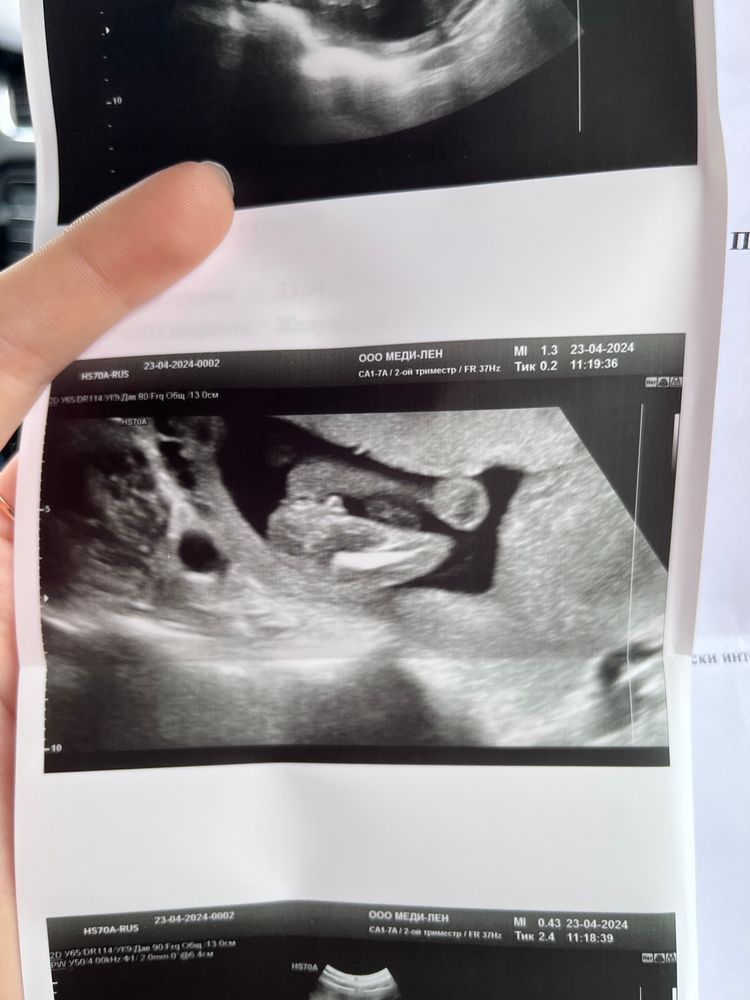

Девочки, привет , есть ли надежда на мальчика ?) Изображение

23.04.2024

Изображение Это мальчик или просто пуповина?